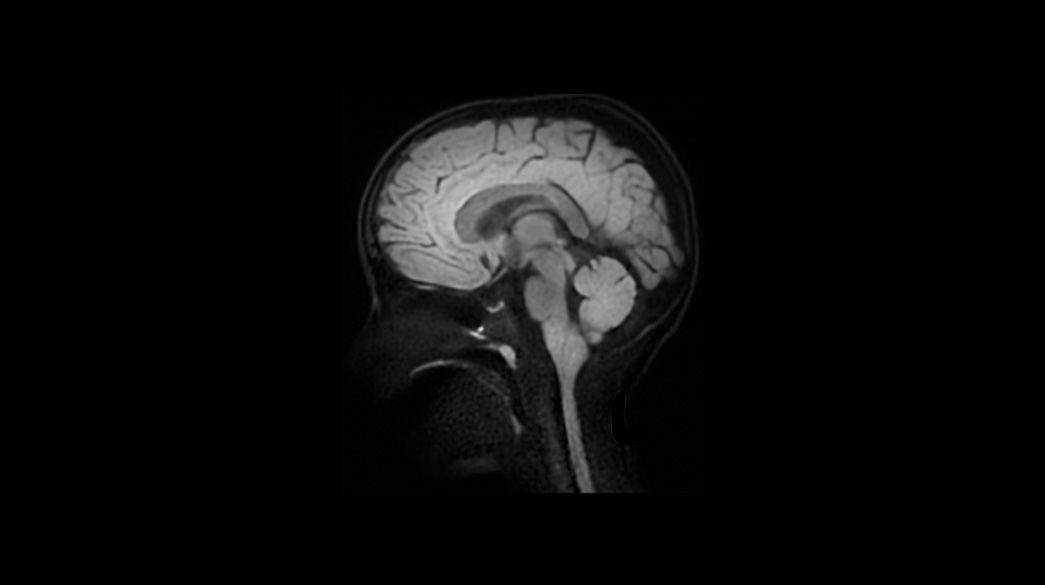

Pediatric MRI imaging applications

Diagnostic confidence and consistency